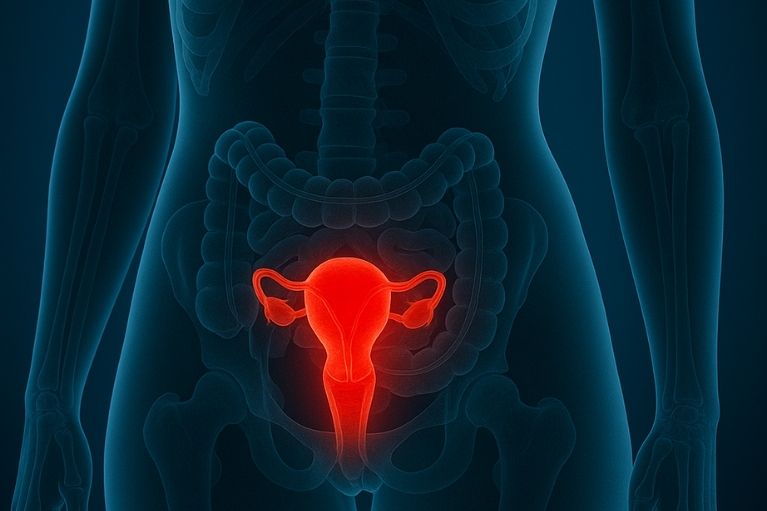

É uma condição em que o tecido da camada interna do útero, que chama endométrio, se aloja fora do útero. Pode acometer o intestino, causando dor para evacuar durante a menstruação.